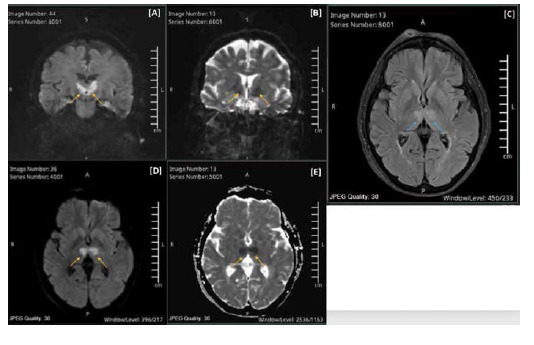

Clinical presentation: We report a case involving a 72-year-old female patient with AOP stroke characterized by a sudden loss of vision, followed by a decreased level of consciousness. Magnetic resonance imaging revealed bilateral thalamic infarcts sparing the midbrain. CTA (computed tomography angiography) revealed a filling defect at the origin of the Percheron artery arising from the left P1 segment. The patient was treated with intravenous thrombolysis. The stroke workup was unremarkable, with a normal thrombophilia workup, a transthoracic echo, and no arrhythmias detected on a prolonged Holter monitor. The patient was treated with aspirin, atorvastatin, and intensive physical and cognitive therapy. On follow-up, she regained her consciousness but exhibited residual impaired vertical eye movements and right-sided dysmetria.